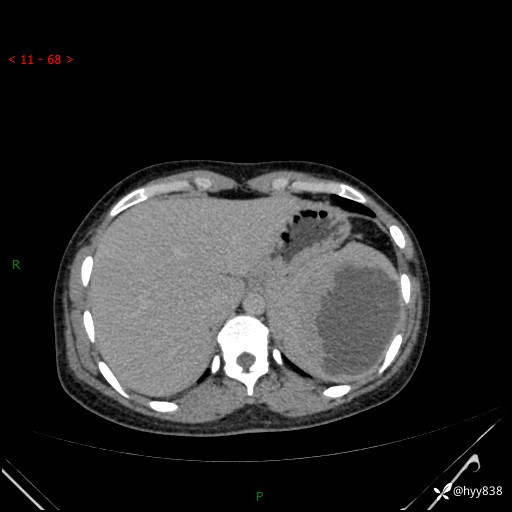

患者性别:男

患者年龄:44岁

主诉:外院超声发现脾脏占位,来我院进一步诊治。

辅助检查:CT

临床诊断:脾脏占位

脾脏CT平扫+增强(动脉期+静脉期)